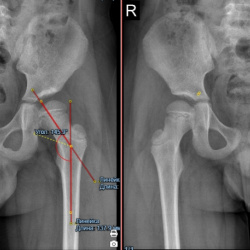

Здравствуйте, подскажите, ребенок 5лет, направили с диагнозом врожденный вывих головки левогобедра слева, 2-сторонний коксартроз. Правильно ли измерил ШДУ, справа Coxa Valga? есть ли признка...